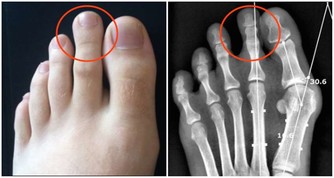

晚上腿腫,變得沒有知覺

這是緩慢靜脈衰竭的表現。需要多吃蔬菜,它們含有能夠加固靜脈壁的纖維。天天可做幾遍腿部保健操。

四肢常常抽筋

這也許是缺鈣和維生素D。它們決定骨骼的硬度和肌肉的縮短。要多吃些奶製品、肝臟、海鮮。